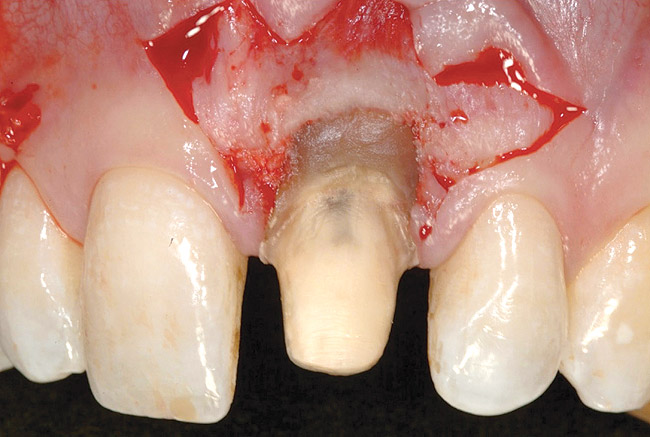

Figure 17  Case Two Initial incision, prepared root surface, and margin alteration.

Figure 17

Before incision, the trimmed acellular dermal matrix was rehydrated in the PRP solution previously obtained. A broad-based, papillary spacing incision was made at the facial of tooth No. 9, followed by a full-thickness, muco­periosteal flap elevation. The facial root surface of the tooth exhibited notches and an uneven root surface. After extensive root planing of the facial root surface with hand planing and rotary instrumentation to eliminate not only the notched root surface but also the pre-existing facial tooth preparation margin, a new chamfer margin was prepared in the tooth 1 mm from the pre-existing margin (Figure 17). This was followed by application of a citric acid solution with a pH of 1 over the facial root surface for 1 minute to aid in sterilization of the root surface.6 Adjustment to the facial aspect of the pre-existing provisional restoration by shortening the facial margin by 1 mm was accomplished, and the provisional restoration was cemented with temporary cement (Figure 18).